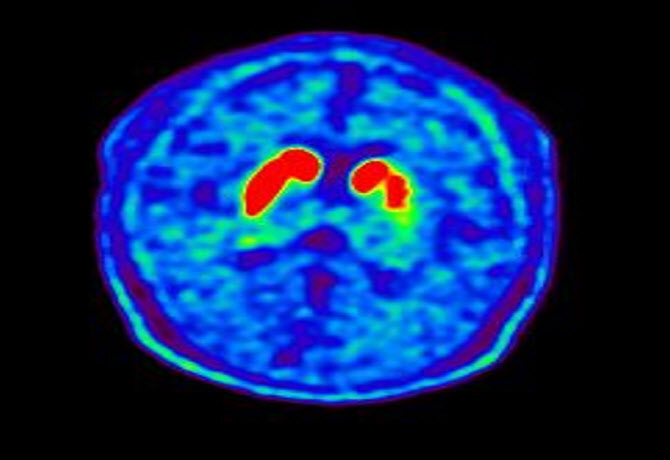

파킨슨병 환자의 뇌 핵의학 영상(도파민 분비 부위 퇴화). |

파킨슨병은 대표적인 퇴행성 뇌질환으로 신경전달물질인 도파민을 비롯한 다양한 뇌 신경세포가 사멸하여 떨림, 경직, 보행장애와 같은 운동 증상과 치매, 망상, 우울증, 자율신경장애, 수면장애 등의 비운동 증상을 보인다. 발병 원인은 정확히 규명되지 않았으나 최근 들어 유전적 요인과 더불어 살충제, 제초제, 금속, 기타 독성 물질 등 환경적 요인도 파킨슨병의 중요한 유발 인자로 제시돼 왔다.